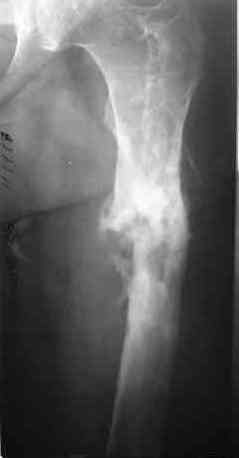

После нескольких некрэктомий, проведения аутодермопластики и заживдения ожоговой раны через 2 месяца после травмы произведен открытый остеосинтез левой бедренной кости штифтом и пластиной (деротационной) [image 01, 02]. Через 1 год и 7 месяцев после травмы у больного диагностированы ложный сустав и хронический остеомиелит левой бедренной кости. Произведено удаление металлических фиксаторов, секвестрэктомия и остеосинтез бедренной костивнешним двухплоскостным стержневым аппаратом [image 03, 04] .

Через 3 года после травмы констатировало отсутствие консолидации бедренной кости, сохранение признаков хронического остеомиелита (свищ в нижней трети левого бедра). Произведен демонтаж аппарата, реостеосинтез бедренной кости спице-стержневым аппаратом, некрсеквестрэктомия. В аппарате удалось лишь частично произвестиустранение углообразной деформации бедренной кости [image 05] .

Через 4,5 лет после травмы выявлены рентгенологические признаки консолидации перелома, признаки хронического остеомиелита купировались. Аппарат был демонтирован. Пациент продолжил ходьбу с дозированной нагрузкой на конечность при помощи костылей. Через 2 месяца начал ходить при помощи трости. Однако, еще через 2 месяца отметил появление свищей на бедре с гнойным отделяемым и укорочение длины конечности. При осмотре в январе 2007 г.: пациент ходит при помощи костылей без опоры на левую нижнюю конечность, на бедре имеются множественные рубцы, на наружной поверхности сегмента в верхней и нижней третях имеются два свищевых хода со скудным серозно-гнойным отделяемым; отечности тканей конечности нет, пальпация безболезненная, отмечается укорочение длины конечности на 5 см, патологическая подвижность не определяется, имеется стойкая разгибательная контрактура коленного сустава (разгибание - 180 гр, сгибание - 170 гр), признаков нарушения кровоснабжения и иннервации тканей конечности нет. Температура тела нормальная. В общих анализах крови и мочи отклонений от нормы нет. [image 06,07, 08 (стрелками отмечены свищевые раны, 09, 10]Дорогие коллеги, я уверен, что у многих из вас после знакомства с данным клиническим наблюдением появится множество вопросов, касающихся уже проведенного лечения (особенно, сроков и способов). Сразу оговорюсь - я не смогу правильно ответить на многие вопросы (особенно касающиеся предшествующего периода лечения). Прошу вас, конечно по возможности, сосредоточить внимание не на разборе допущенных ошибок (проведенного лечения), а помочь добрым советом относительно тактики наших дальнейших действий. Наверное, кто-то располагает бесценным опытом лечения подобной патологии.